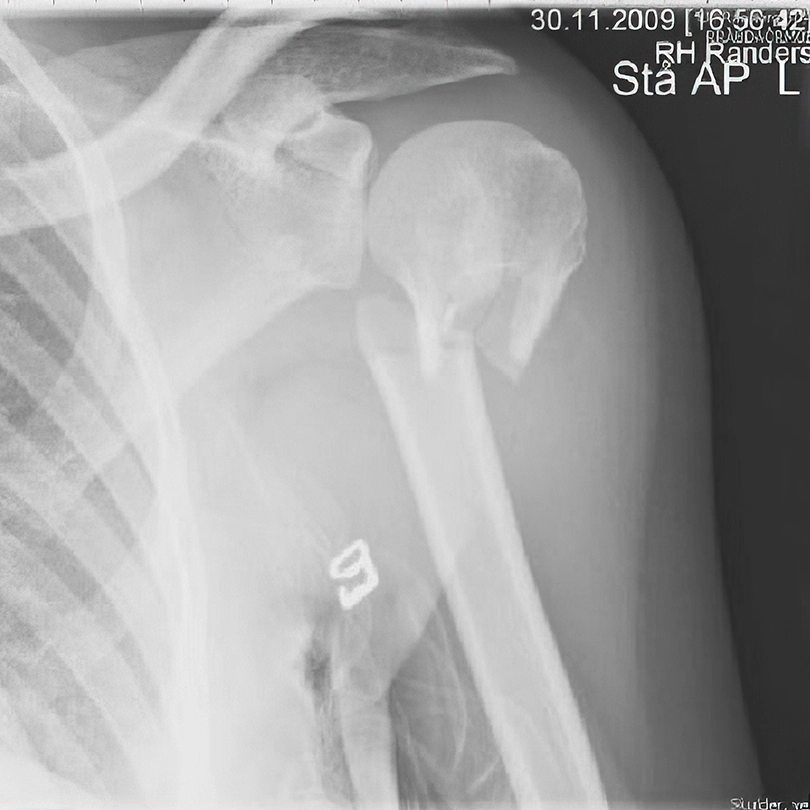

Prelom gornjeg dela nadlaktice

Prelom gornjeg dela nadlaktice javlja se najčešće kod starije populacije (preko 65 godina). Ukoliko je u pitanju prost prelom nadlaktice (tzv. dvodelni prelom nadlaktice) i ukoliko je položaj koštanih fragmenata zadovoljavajući, lečenje je konzervativno – trouglom maramom. Ukoliko je prelom nadlaktice iz više fragmenata, oni su često pomereni (dislocirani) i tada se preporučuje hirurška intervencija. Najčešće se pod pojmom preloma ramena podrazumeva ovaj prelom.

Prelom gornjeg okrajka nadlaktice (humerusa), rendgenski snimak

Prelom humerusa